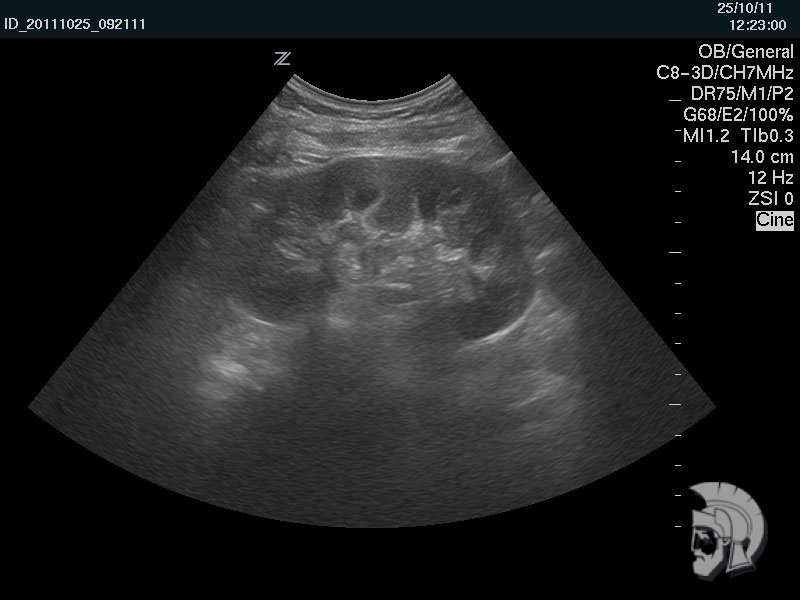

3D-фото мочевого пузыря.

«Камень» 4.5 мм в диаметре в мочевом пузыре мужчины 50 лет. «Камень» указан стрелкой |